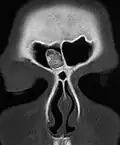

Osteoma